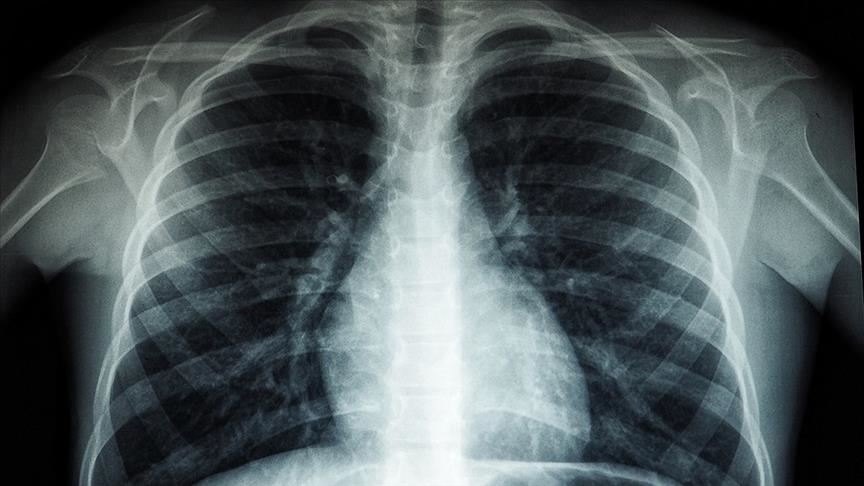

Drejtori Rajonal i Organizatës Botërore të Shëndetësisë (OBSH) për Evropën, Hans Kluge, njoftoi se 1 milion njerëz vdesin çdo vit nga tuberkulozi, “sëmundja infektive më vdekjeprurëse në botë” Kluge ndau...

OBSH-ja: Tuberkulozi është sëmundja infektive më vdekjeprurëse në botë, vret 1 milion njerëz çdo vit

Gjenevë Drejtori Rajonal i Organizatës Botërore të Shëndetësisë (OBSH) për Evropën, Hans Kluge, njoftoi se 1 milion njerëz vdesin çdo vit nga tuberkulozi, "sëmundja infektive më vdekjeprurëse në botë",...